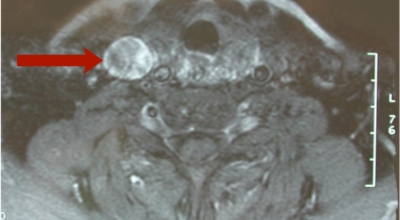

갑상선은 우리의 인체에서 여성・남성호르몬 및 부신 피질 호르몬과 같은 호르몬을 분비하는 역할을 해요. 호르몬을 분비하는 장기를 내분비 기관이라고 하네요. 갑상선은 내분비 기관 중 한 개로 주로 해초류와 같은 음식물에 함유되어있는 요오드를 원료로 호르몬을 합성해요. 갑상선은 나비모양의 내분비선으로 보통 목의 앞 아래에 위치하여 갑상선 호르몬을 분비해요.

갑상선에서 호르몬의 합성과 분비가 저하된 경우, 표적 조직의 작용 이상에 의해 호르몬이 작용하지 않는 경우 양쪽 모두가 있어요. 갑상선 호르몬이 저하되는 경우에는 갑상선 자체에 원인이 있는 원발성 갑상선 기능 저하증(하시모토 병 등)과 뇌 기능 저하에 원인이 있는 중추성 갑상선 기능 저하증이 있고 호르몬 이상이 없는 경우는 갑상선 호르몬 불응증이라고 하네요. 뇌의 문제로 인해 생기는 경우는 시상하부나 뇌하수체에 종양, 감염, 유육종증 또는 암 전이가 생겼을 때로 알려져 있어요.